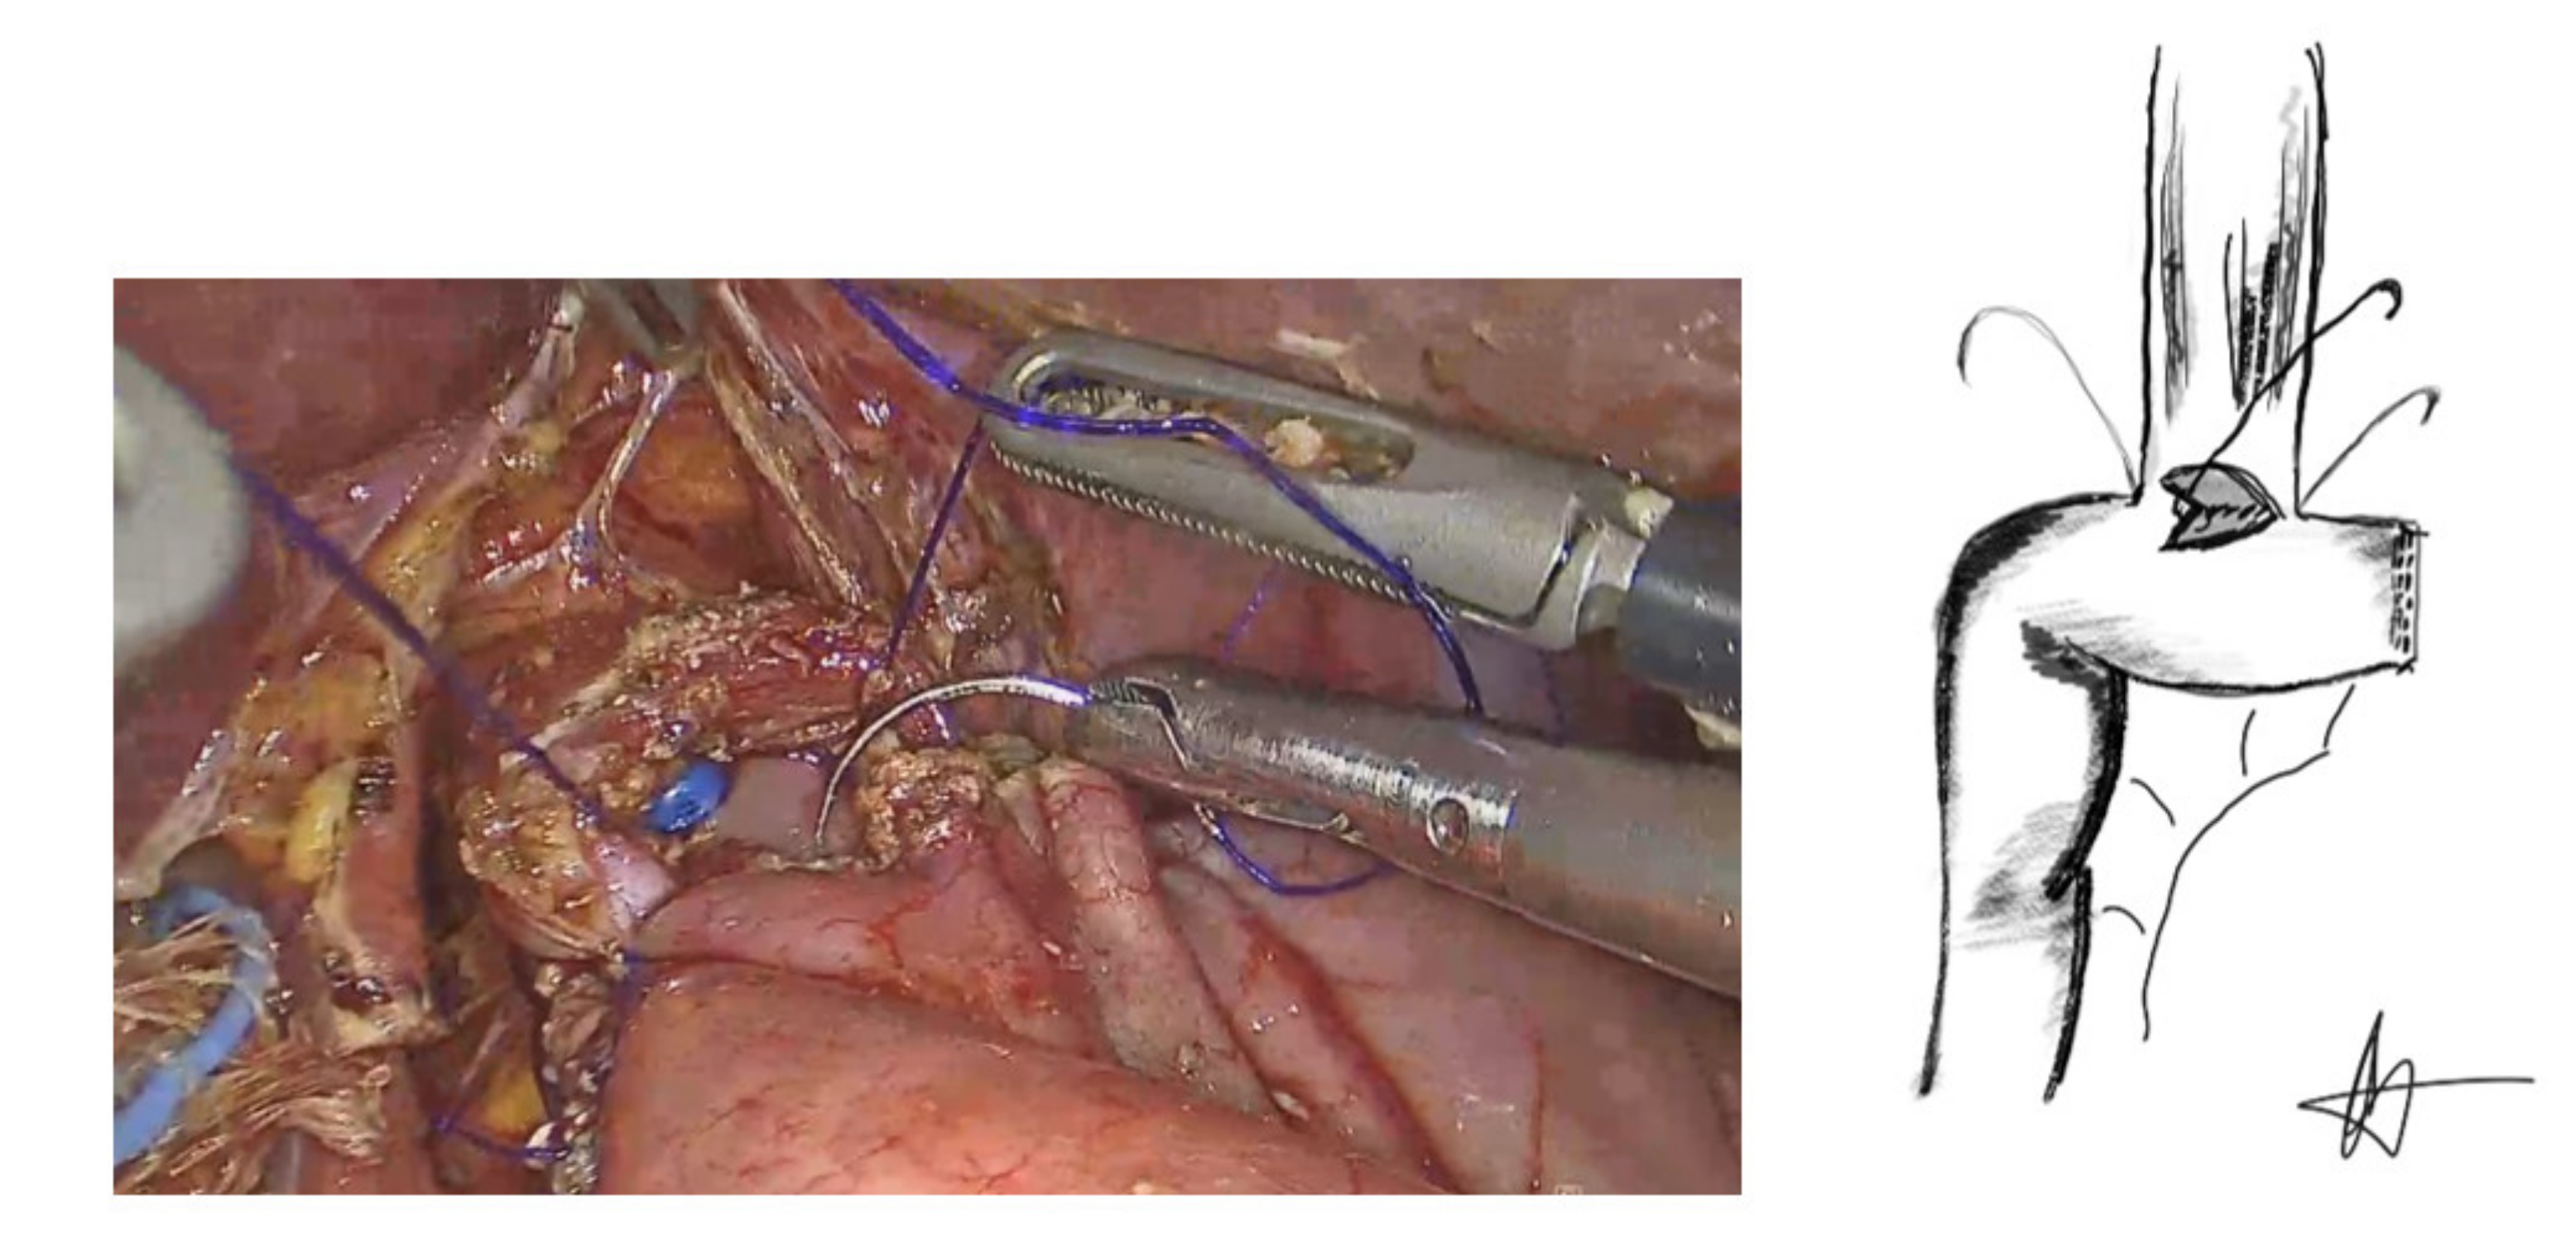

2.2. Laparoscopic Hand-Sewn Esophago-Jejunal Anastomosis